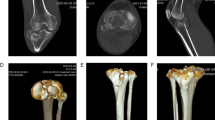

Developing PlaTiF was a collaborative effort involving engineers, radiologists, and orthopedic surgeons. We curated a heterogeneous collection of anterior-posterior radiographs from 186 patients, ensuring our dataset captured the real-world diversity of these injuries.

The process wasn't just about collecting images; it was about precision. Expert surgeons and radiologists meticulously classified each fracture using the Schatzker system, providing a "gold standard" for AI training. Beyond classification, we also generated detailed tibial bone masks for every image. These masks are a vital feature of PlaTiF, as they allow AI models to perform automated fracture assessment and morphological analysis with much higher accuracy.